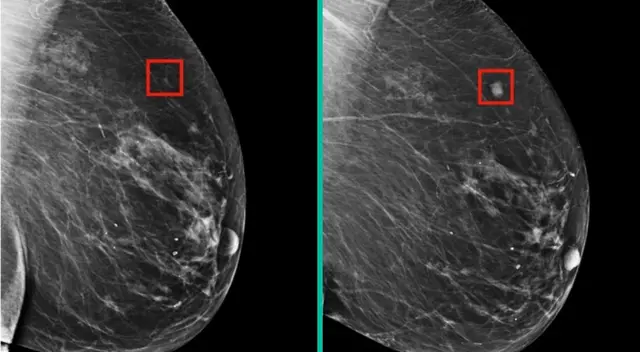

En esa misma línea, el Instituto de Tecnología de Massachusetts (MIT) ha desarrollado una tecnología de inteligencia artificial (IA) que puede detectar la presencia de células cancerosas en los tejidos mamarios antes de que se desarrollen en tumores visibles.

Los investigadores del MIT señalan que el sistema es capaz de detectar el cáncer hasta cuatro o cinco años antes de que se vuelva visible en una mamografía estándar. La tecnología de detección temprana de cáncer de mama ya existente, como las mamografías y la resonancia magnética, son efectivas, pero a veces pueden dar falsos positivos o negativos, lo que lleva a pruebas adicionales y aumenta el estrés y la ansiedad de las pacientes. Sin embargo, gracias a esta nueva tecnología permitiría una detección más temprana y precisa.

De acuerdo, a los investigadores del MIT, la nueva tecnología de IA y su aplicación en el campo de la salud podría salvar muchas vidas en el mundo. Asimismo, se sabe que el sistema fue evaluado en un grupo separado de pacientes y se encontró que era capaz de detectar el cáncer de mama con una precisión del 94,5 %.